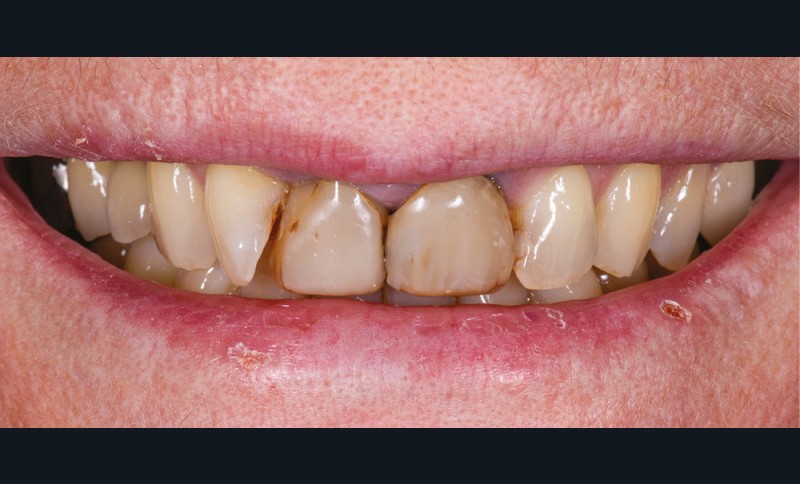

Présentation du cas (fig. 1 et 2)

Une patiente de 55 ans se présente pour une prise en charge esthétique de son sourire. Sa demande regroupe à la fois la teinte, l’encombrement incisivo-canin et l’asymétrie des incisives centrales.

Les deux incisives centrales ont été traitées endodontiquement plusieurs années auparavant et restaurées par des composites directs.

Le contrôle de plaque est insuffisant et nous notons une perte d’attache entre 12 et 11.

La patiente refuse d’emblée tout traitement orthodontique, même par aligneurs.